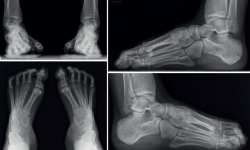

Figura 3. En las radiografías que se presentan se objetiva una deformidad importante y bilateral en cavo varo. En esta proyección lateral de radiografía en carga se observan signos de varización subtalar: seno del tarso abierto, subastragalina posterior en proyección ortogonal, columna medial sobre columna lateral, supinación del antepié. El paciente manifestaba una rigidez importante en el conjunto tobillo-pie y una sobrecarga lateral con dolor en el quinto radio.